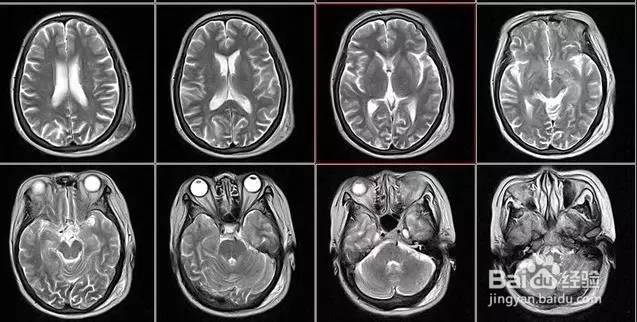

核磁共振:摇一摇再看

核磁共振机使用较强大的磁场,使人体中所有水分子磁场的磁力线方向一致,这时磁共振机的磁场突然消失,身体中水分子的磁力线方向,突然恢复到原来随意排列的状态。简单说就相当于用手摇一摇,让水分子振动起来,再平静下来,感受一下里面的振动。所以,核磁共振(MRI)也被戏说为是摇摇看的检查。